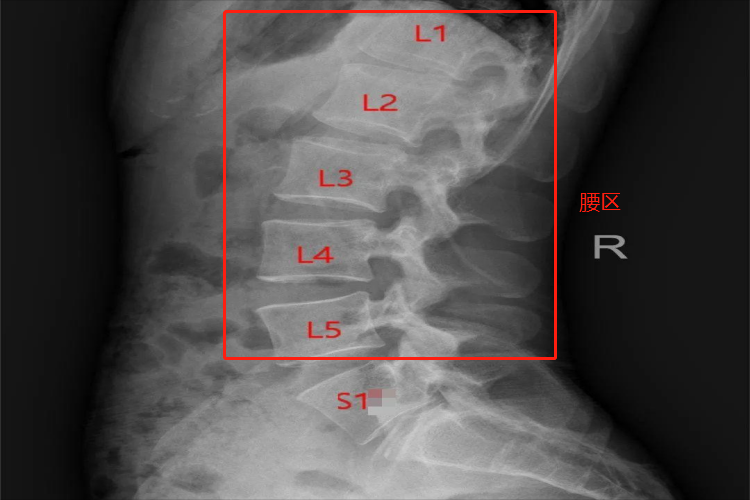

腰部位置一般指的是腰区,位于躯干部,上界为胸背区下界,下界为两髂嵴后份和两髂后上棘的连线,主要由腰椎、韧带等共同构成。

腰部即腰区,位于人体躯干部,上界为胸背区下界,下界为两髂嵴后份和两髂后上棘的连线。主要由皮肤、浅筋膜、深筋膜、肌层、血管神经等软组织和腰椎柱(介于脊柱胸椎尾侧与骶尾椎之间,是腰部脊柱的骨性结构)等共同构成。